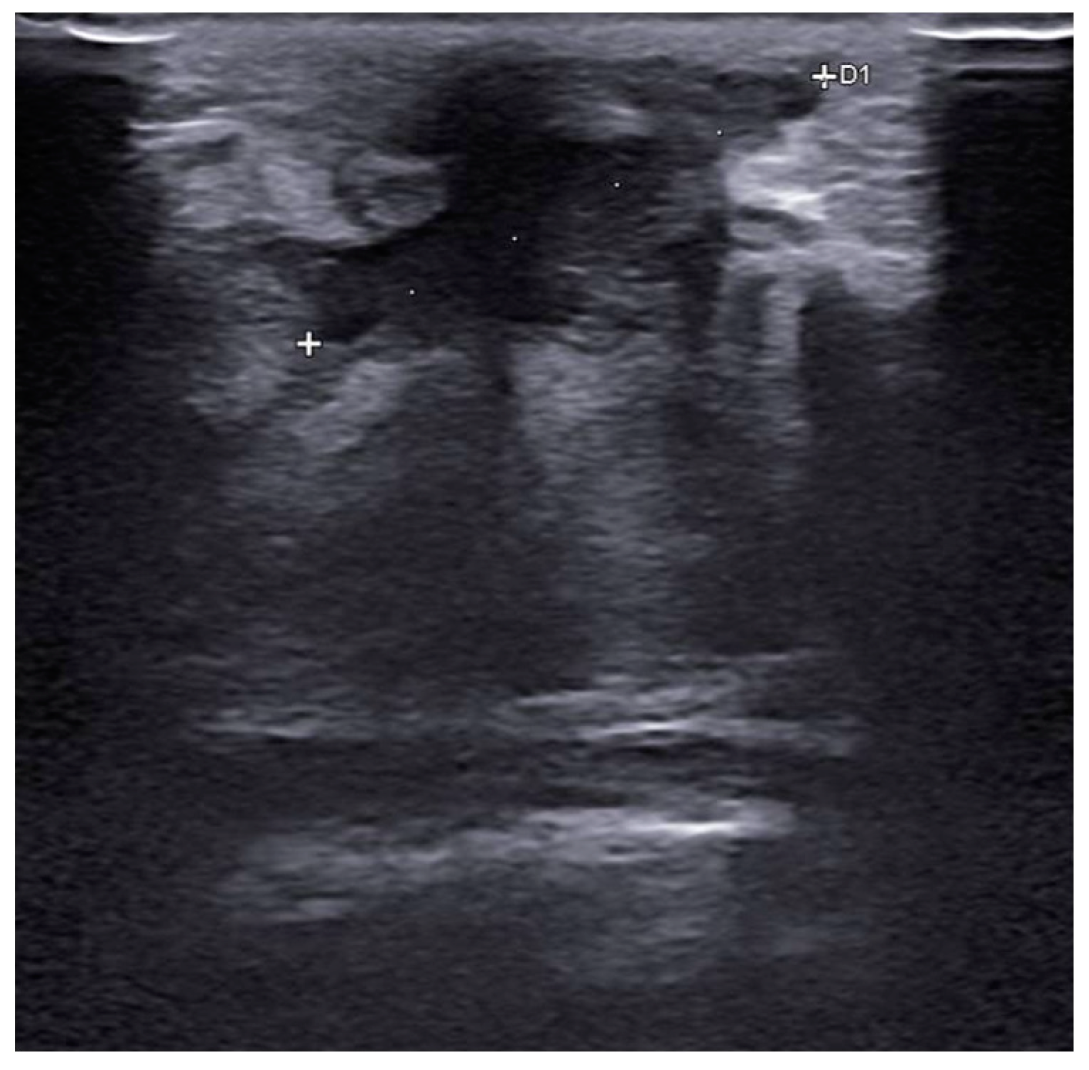

Before surgery, all patients underwent breast ultrasound to assess the presence of an abscess or fistula. Regarding clinical and radiological presentation, 12 patients presented with an abscess in the form of a painful and tender breast mass, with tense and reddened skin but no cutaneous fistula, confirmed by ultrasound (Figure 1, Figure 2 and Figure 3); two patients presented with an abscess associated with periareolar fistula (Figure 4), visible on breast ultrasound; five patients showed signs of a past abscess with negative preoperative ultrasound findings, and among them, one had a fistulous tract without purulent discharge (Table 1). The location of abscesses, fistulas, and their sequelae was the periareolar area in all patients. Additionally, four patients presented with bilateral symptoms. For patients with active abscesses at surgery, the mean size of the abscess cavity was 28.7 mm.

Figure 1. Abscess measuring approximately 16 mm × 2.5 mm in extent, without a liquid component, located in the retroareolar region.